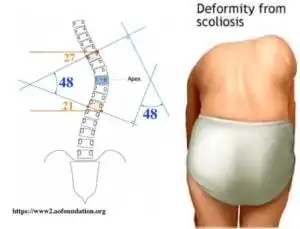

脊柱侧弯最佳睡姿vs最差睡姿

脊柱侧弯注意睡姿能矫正侧弯吗

脊柱侧弯最全的康复训练方案

脊柱侧弯纠正大法多图详解,赶紧转走

体检发现脊柱有侧弯,该如何改善

值的医疗脊椎侧弯矫正一定要改变侧面姿势,否则徒劳无功